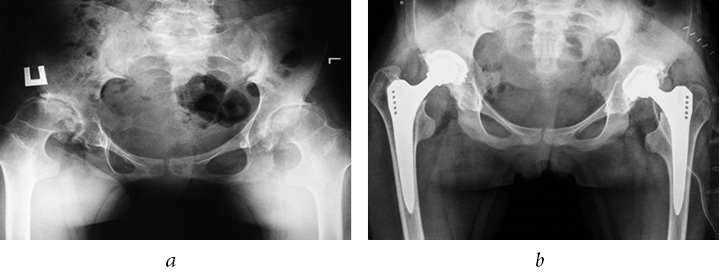

Stabilometric and plantographic studies were conducted in 12 pediatric patients with bilateral coxarthrosis, stage III, which developed as a result of HP dysplasia in 6 patients and spondyloepiphyseal dysplasia in 6 patients. The age of the patients ranged from 13 to 17 years (average age was 15.1 ± 0.47 years). The examinations were performed before (Fig. 1, a) and after (Fig. 1, b) the bilateral THR within 1–3 years. The time interval between surgeries on the contralateral joints ranged from 6 to 12 months.

Fig. 1. Radiograph of the hip joint (HP) of patient A, 16 years old. Spondyloepiphyseal dysplasia. Bilateral coxarthrosis, stage III: a — before hip replacement; b — after bilateral THR